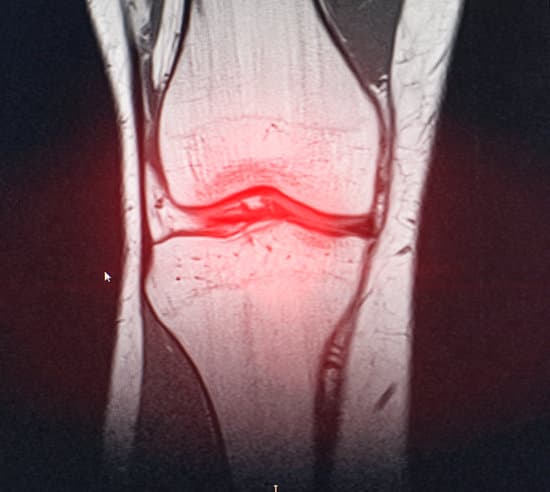

무릎 연골 손상: 원인, 증상, 치료 방법에 대한 완벽한 가이드

무릎 연골 손상은 관절을 보호하는 연골이 손상되거나 마모되는 상태로, 무릎에 가해지는 충격이나 과도한 사용으로 인해 발생할 수 있습니다.

연골은 관절을 매끄럽게 움직이도록 도와주며, 충격을 흡수하는 중요한 역할을 합니다.

그러나 연골은 혈액 공급이 제한되어 있어 손상 시 자연 치유가 어렵기 때문에 조기 진단과 적절한 치료가 중요합니다.